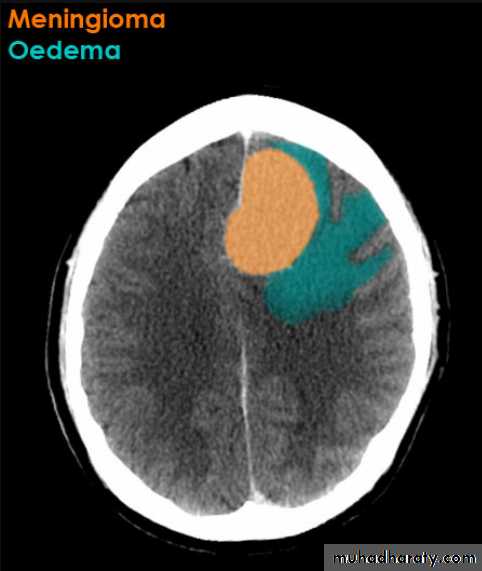

Meningioma

CT finding

meningioma presented as isodense area or slightly hyper density area with surrounded crescent of hypo density ( csf cap ) post contrast injection the lesion enhance homogeneously with enhancing Dural tail .

it may be associated with little or no peri focal edema .